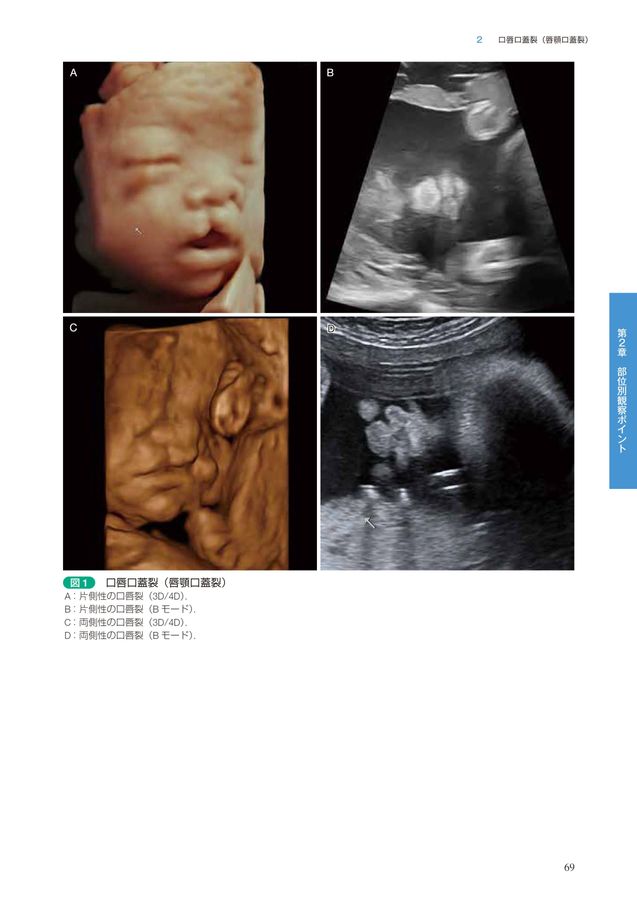

胎児診断から始まる口唇口蓋裂 集学的治療のアプロ-チ/メジカルビュ-社/小林眞司(単行本) 胎児診断から始まる 口唇口蓋裂−集学的治療のアプローチ | 小林の詳細情報

胎児診断から始まる 口唇口蓋裂−集学的治療のアプローチ | 小林。口唇裂・口蓋裂治療の手引 改訂第3版 |本 | 通販 | Amazon。0161-726x1024.jpg。

口唇口蓋裂の手術治療② 口蓋裂 | メディカルノート

口唇口蓋裂の手術治療② 口蓋裂 | メディカルノート